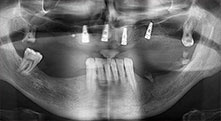

For what indications do you use the saws?

Bratu: We routinely use the instruments for harvesting bone blocks and splitting alveolar ridges. We also use the Piezomed B6/B7 for osteotomy of impacted teeth and removing failed implants. All indications that require deep, clean cuts.

Bratu: We like to use the sandwich technique for augmentation in the lateral mandible. A bone cover is prepared with the piezo saw and the crestal fragment is fixed with microscrews. We place a mixture of autologous bone and xenogenic bone replacement material in between. This works very reliably. You should always ensure sufficiently dimensioned vertical cuts when splitting the alveolar ridge in the mandible. Otherwise the bone may fracture easily.